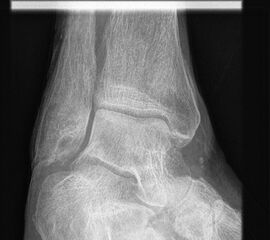

Sprunggelenk ap, Mortise-View und lateral mit Belastung

Indikation:

• Nach Trauma (nur wenn Belastung des Fußes möglich), Weichteilverletzungen, entzündliche, degenerative, tumoröse und andere schmerzhafte Erkrankungen. Insbesondere zur Beurteilung der Achsenverhältnisse am Sprunggelenk sind belastete Aufnahmen zwingend erforderlich (z.B: Planungsaufnahmen für Endoprothetik Sprunggelenk oder vor einer Achskorrektur). Zur anterior-posterioren Darstellung wird üblicherweise die Mortise-Aufnahme verwendet und nicht die ap Aufnahme mit gerade gestelltem Fuß.

Sprunggelenk ap mit Belastung

Positionierung:

• Der Patient steht, beide Beine sind geleichmäßig belastet.

• Die Fußachse verläuft parallel zum Zentralstrahl.

• Der Zentralstrahl ist zentral auf den Gelenkspalt des oberen Sprunggelenks ausgerichtet.

• Die Röntgenkassette liegt dem Fuß dorsal an.

Kennzeichen des Röntgenbildes:

• Darstellung des Talusdoms mit lateraler Überlagerung durch die Fibula.

• Das Sprunggelenk befindet sich dabei in 90° Stellung.

• Der Weichteilmantel ist erkennbar.

Besondere Bemerkungen zum Beispielbild:

• Subfibulare Verkalkung nach mehreren Distorsionen.

• Gut erkennbar ist die für eine ap Aufnahme typische Überlappung von Fibula und lateralem Talus.

Zur Vollansicht und zum Lesen der Bildbeschreibung bitte die Bilder anklicken.

Sprunggelenk Mortise-Aufnahme mit Belastung

• Der Fuß wird um ca. 20° innenrotiert. Der Zentralstrahl ist mittig auf den Gelenkspalt des oberen Sprunggelenks ausgerichtet.

• Überlagerungsfreie Darstellung des Talus und der Malleolengabel.

• Der Gelenksspalt zwischen Talus und Fibula sowie zwischen Talus und Innenknöchel zeigt eine identische Breite.

• Zustand nach Fremdkörperverletzung.

• Die röntgendichte Struktur (Metall) befindet sich im Bereich der lateralen Kalkaneuswand.